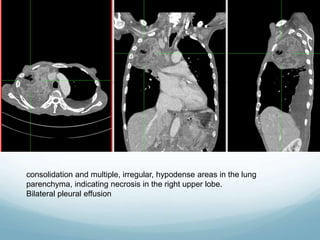

Chest Xray (16/10/2018)

CECT Thorax (1.11.2018)

consolidation and multiple, irregular, hypodense areas in the lung

parenchyma, indicating necrosis in the right upper lobe.

Bilateral pleural effusion

consolidation and multiple,irregular, hypodense areas in the lung parenchyma, indicating necrosis in the right upper lobe. Bilateral pleural effusion

• #12 Patchy area of consolidation at right upper zone with thickened oblique fissure

• #14 Plain chest radiograph Consolidation in the right mid to upper zones with area of lucency (cavitation)   Bulging of fissure